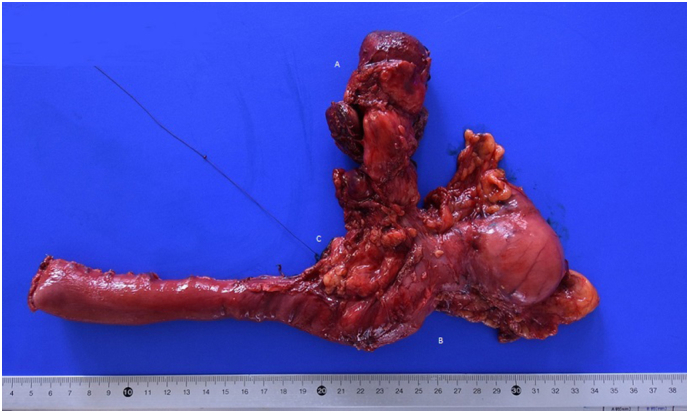

The patient underwent a Whipple’s cephalic duodenopancreatectomy, associated with a radical excision of gallbladder with hepatic resection of IVb and V segment, due to intraoperative suspicion of gallbladder cancer involving the CBD (Fig. 4). The intervention was performed by an expert surgeon specialized in hepatic, biliary and pancreatic surgery.

Final pathology report revealed the presence of three distinct cancers, respectively: moderated differentiated adenocarcinoma of gallbladder (Fig. 5) with invasion of cystic duct and hepatic tissue; moderately differentiated adenocarcinoma of mild CBD with serosa invasion (Fig. 6); Vater’s papilla moderately differentiated adenocarcinoma with sub-mucosal extension (Fig. 6). Gallbladder and CBD adenocarcinoma showed perineural and microvascular infiltration. Microscopic examination didn’t detect any direct continuity between the three tumors. Metastasis were identified in the pancreaticoduodenal, peri-hepatic and peri-gastric lymph nodes.